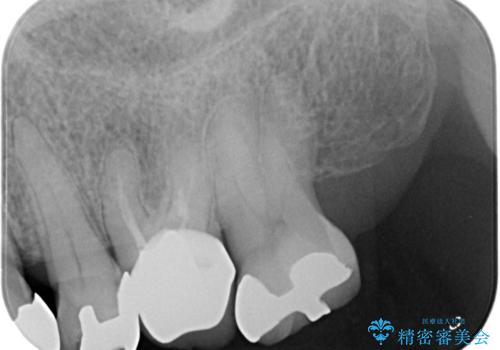

- 左下の大臼歯(6番)の根の治療を行いました。

後方の歯が欠損していた為、インプラントをお勧めしましたが希望されませんでした。

左下6番の根管治療は六本木院の林院長にお願いしています。

左上56間が狭かったため、写真にはないですが、セパレーションを2回ほど行い、歯根間距離を広げてから処置を行っています。

歯と歯の間(特に歯根と歯根の間)が異常に狭いと歯型が正確にとれない上に歯間ブラシも入らないような歯の形態になり、セルフケアに支障がでてきます。